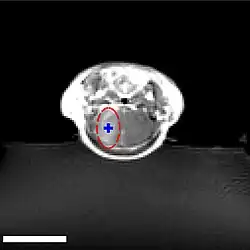

Der Fokus des Ultraschalls kann auf beliebige Areale im Gehirn gerichtet werden. Dadurch kann die Blut-Hirn-Schranke selektiv, auf bestimmte Hirnareale begrenzt, geöffnet werden. So können applizierte Wirkstoffe gezielt in diese Areale diffundieren.[140] Die behandelten Areale lassen sich durch eine simultan laufende Magnetresonanztomographie (MRT) genau verfolgen. Dabei dringt das für die MRT verwendete Kontrastmittel, beispielsweise Gadopentetat-Dimeglumin, nur durch die geöffneten Areale der Blut-Hirn-Schranke in das Gehirn ein. Diese Bereiche werden dadurch im MRT deutlich sichtbar hervorgehoben. Das hochpolare Gadopentetat-Dimeglumin ist nicht in der Lage die ungeöffneten Bereiche der Blut-Hirn-Schranke zu passieren.

Im Tiermodell Maus werden bei der Anwendung von fokussiertem Ultraschall mit Mikrobläschen Frequenzen im Bereich von 0,5 und 2 MHz[141] mit kurzen Pulslängen im Millisekundenbereich und Wiederholfrequenzen im Bereich von 1 Hz, über einen Zeitraum von weniger als einer Minute angewendet.[142] Der optimale Frequenzbereich liegt unterhalb von 1 MHz.[143] Die akustische Leistung beträgt weniger als ein Watt. Die verwendeten Mikrobläschen sind meist zugelassene Kontrastmittel aus der kontrastmittelverstärkten Sonographie. Sie haben typischerweise einen Durchmesser von 3 bis 4,5 µm, bestehen beispielsweise aus Humanalbumin und sind mit Perfluorpropan oder ähnlichen Schwergasen gefüllt.[144]